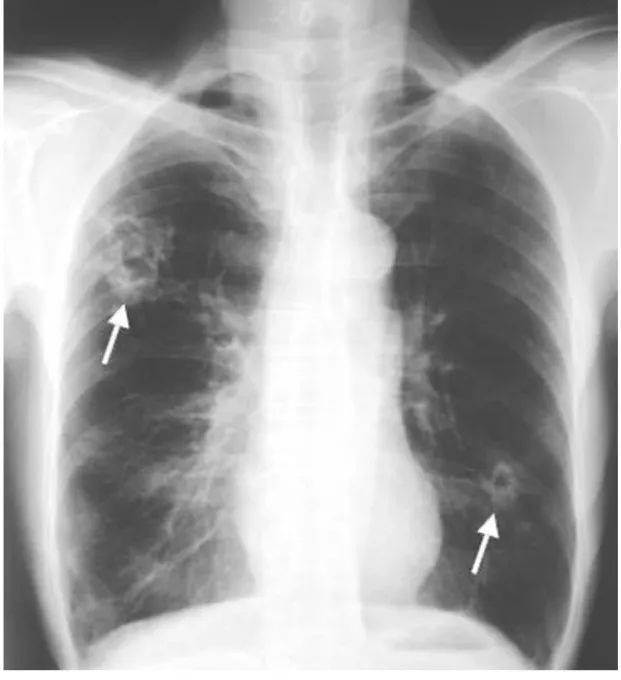

直到5月22日,小A因为近期睡眠不好,又再做了次进行了寄生虫检查,结果呈阳性。在他的体内,检测到了四种寄生虫!!!

医生对小A解释说,寄生虫可能会寄生到全身各处,且没有特效药,要是住院的话还可以想办法治疗......